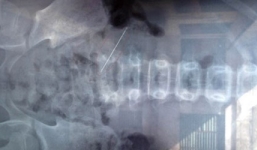

Một bé trai bị sốt xuất huyết, đông máu, suy hô hấp nặng có nguy cơ tử vong đã được cứu sống thành công.